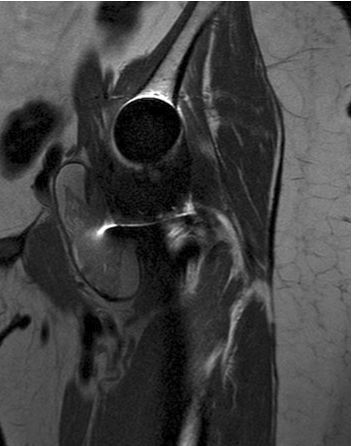

• MRI with Metal Artifact Reduction Sequence (MARS)

• findings

• a pseudotumor will appear like a fluid collection or solid mass in periprosthetic soft tissues

• T1 weighted images will show signal similar to bladder contents (transudate)

• T2 weighted images will generally show hyperintensity as compared to muscle and may be heterogenous or homogenous

• the hypointense content observed in T2 sequences may be related to the presence of necrosis or metal deposition